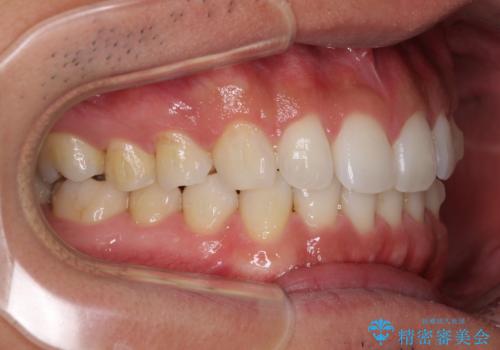

- 上下前歯のデコボコを気にして来院された患者様です。

以前矯正をした後戻りということで、歯列不正はそれほど大きくなかったため、インビザライン・ライトを用いて矯正治療を行うこととしました。

1日22時間以上しっかりと装着してくださったので、半年かからずに治療を終えることができました。